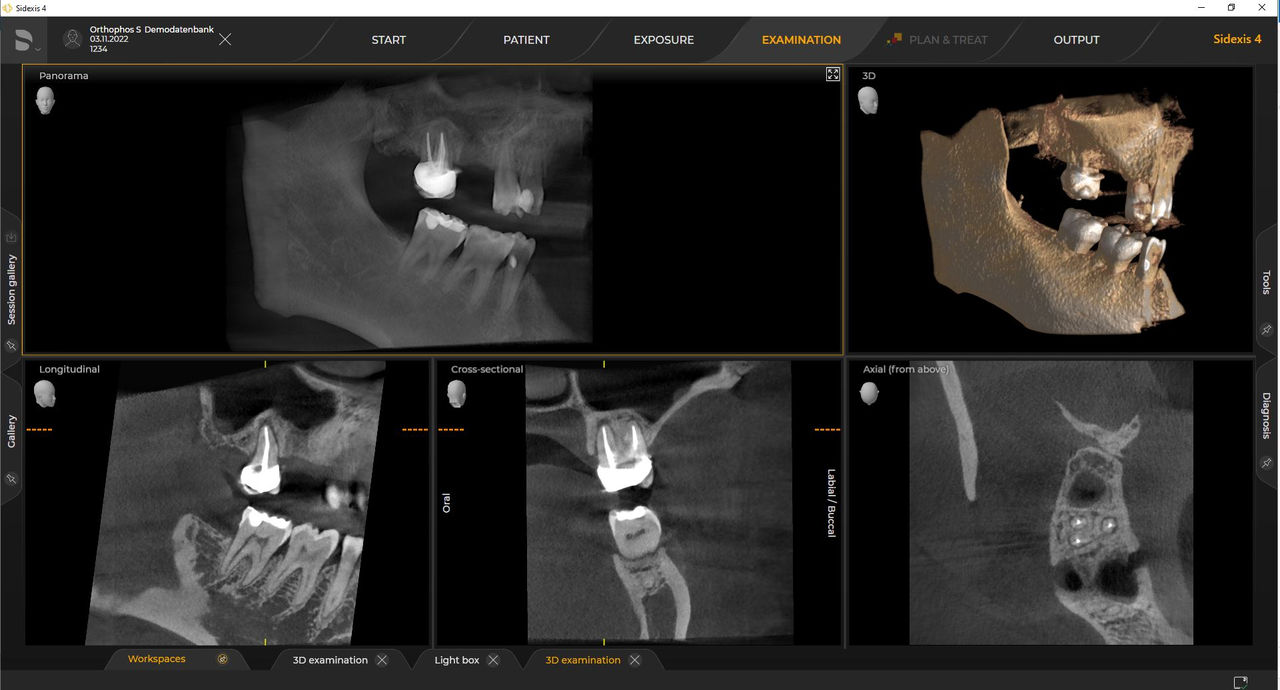

Las unidades de radiología de Dentsply Sirona funcionan exclusivamente con Sidexis 4. Sin embargo, la migración de datos de Sidexis XG a Sidexis 4 es muy fácil. Sidexis 4 permite una experiencia digital completa con las últimas herramientas

Con el modo de dosis baja inteligente 3D, obtiene imágenes 3D en el rango de dosis de una imagen radiológica 2D. En el modo HD (hasta 1400), las imágenes individuales se obtienen durante una única rotación y se convierten en un volumen 3D con hasta 80 μm para imágenes de bajo ruido en alta resolución.